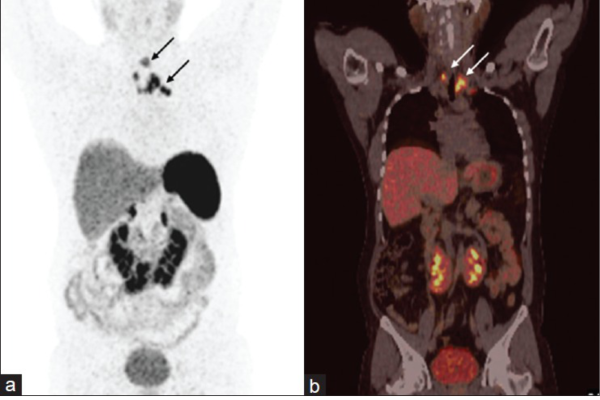

DOTANOC

68-Ga DOTANOC PET-CT is an advanced nuclear imaging technique specifically designed for the detection and evaluation of neuroendocrine tumors (NETs). It works by targeting somatostatin receptors, which are commonly overexpressed in these tumors. This scan provides high-resolution images that help in localizing the primary tumor, assessing the extent of disease spread, and evaluating suitability for treatments like Peptide Receptor Radionuclide Therapy (PRRT). It is particularly valuable in managing gastroenteropancreatic tumors, paragangliomas, pheochromocytomas, and other NET-related conditions.

Key Indications:

• Gastroenteropancreatic tumors (Carcinoids, Insulinomas)

• Pheochromocytoma and Paraganglioma

• Medullary thyroid carcinoma

• Meningioma and other neuroendocrine tumors